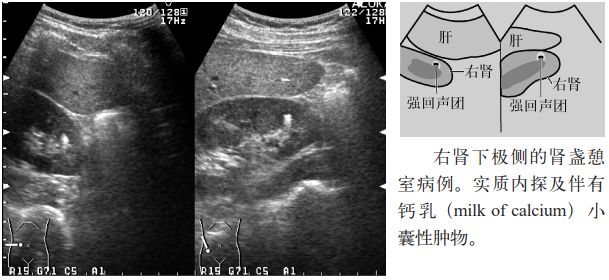

3.肾盏憩室或肾盏积水的内部常见沉积物样高回声(钙乳)或结石。

图6 钙乳